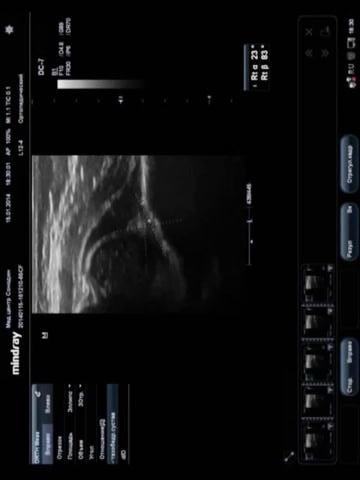

- Двухсторонний вывих тазобедренных суставов новорожденного.

Конечно здесь тип 4 т.е вывих, т.е угол А=23, В=83 гр.

Выставил заключение: Двухсторонний вывих тазобедренных суставов. Тип-4.

Я расценил, что головки располагаются вне полости сустава.

Наш коллектив склонен отнести данный тип сустава к 3Б типу. Интересны и функциональные пробы при данном типе сустава. В любом варианте для ортопеда данное обследование -- неоценимая помощь, т.к. позволяет применить ортопедические приспособления гораздо раньше. В 3 месяца сделают рентгенограммы таза в прямой проекции и, возможно, в отводящих приспособлениях. Тут, к сожалению, УЗИ поможет мало (в передне-задней плоскости).

Наш коллектив склонен отнести данный тип сустава к 3Б типу.

Значит, все таки тяжелый подвывих.

Ладно, думаю что между типом 3Б и 4 принципиальной разницы нет.